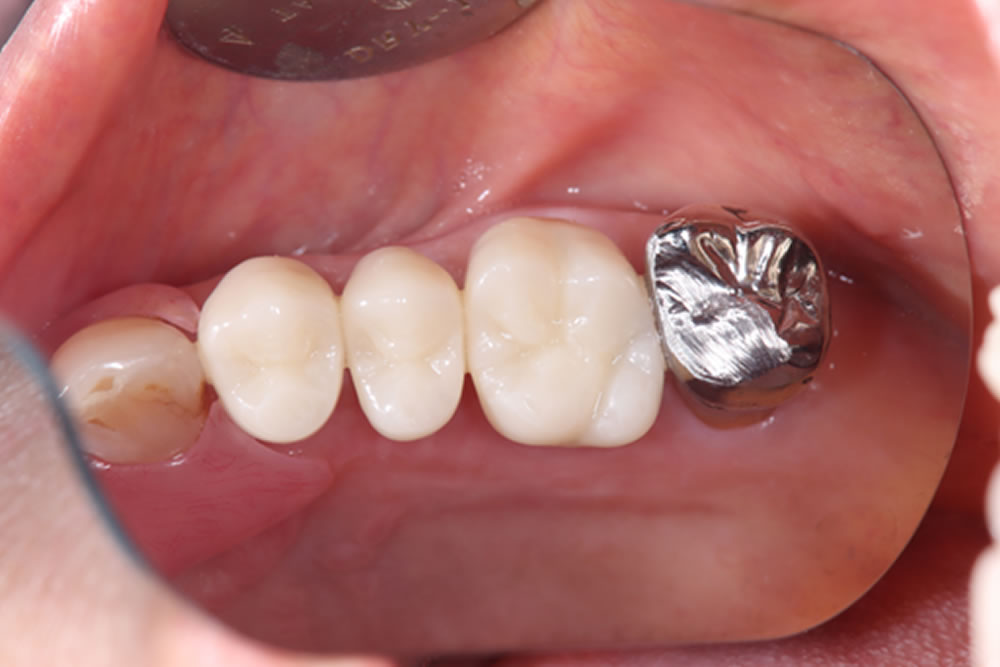

上部構造の装着・治療完了

3ヶ月後に二次オペを行い、その後の歯肉の状態を確認したところ、周囲歯肉に炎症は認められませんでした。

また、奥の銀歯についてもセラミックへの置き換えを希望されていたため、同時につめ物の作成を行いました。

治療前後の比較

奥歯の痛みも消失し、快適に噛めるようになったとのことでした。また、最終的にはメタルフリーな口腔内となり、カリエスリスクの低減、審美性が向上しました。